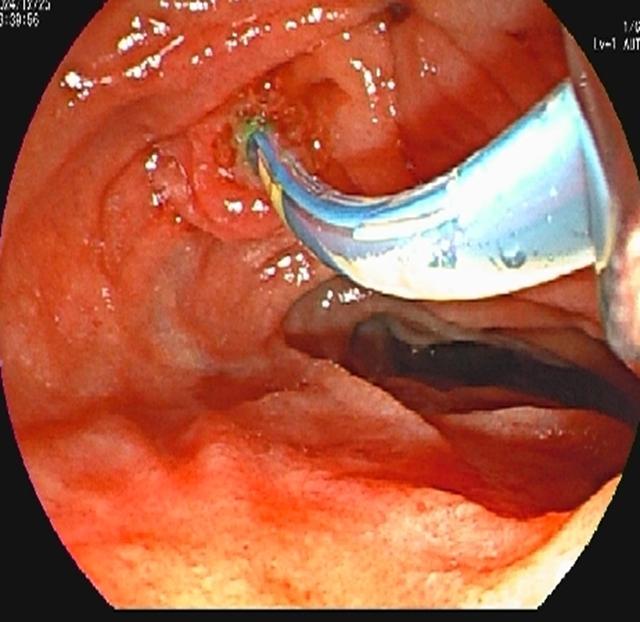

内镜到达十二指肠乳头时,切开乳头的瞬间,大量白色脓液喷涌而出(证实胆道高压、感染极重);随后用球囊扩张乳头(扩大开口),顺利取出嵌顿的结石。

内镜逆行胰胆管造影的关键操作是乳头切开引流+取石:医生用微型电刀切开狭窄的乳头(类似“扩大下水道口”),再用网篮或球囊取出结石。从切开到取石,通常仅需10-30分钟,能迅速降低胆道压力,让淤积的脓性胆汁通过切口及鼻胆管流出体外—这是控制感染、逆转休克的关键。